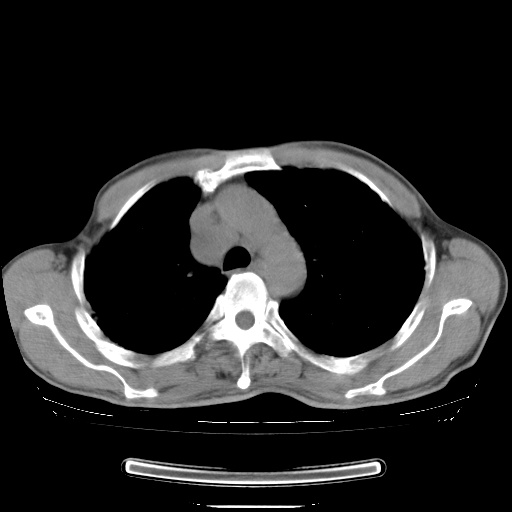

男性患者,63岁。右侧胸背部疼痛2月,加重一周。

考虑:右肺中央型肺癌并右肺下叶不张;两肺尖继发性肺结核。

还有----下叶不张   挺典型

右下中央型肺癌伴肺内纵膈转移。

右下肺中心型肺癌并肺不张

右肺下叶支气管狭窄闭塞,右下肺不张,气管前间隙淋巴结肿大,两上肺散在分部粟粒灶,沿肺血管支气管束分部,血管支气管束走形较为光滑。考虑右肺中心型肺癌合并肺不张,纵隔淋巴结转移,两上肺癌性淋巴管炎

右肺下叶中心性肺癌并纵隔淋巴结转移,左侧肋骨转移。双肺上叶继发性结核表现。